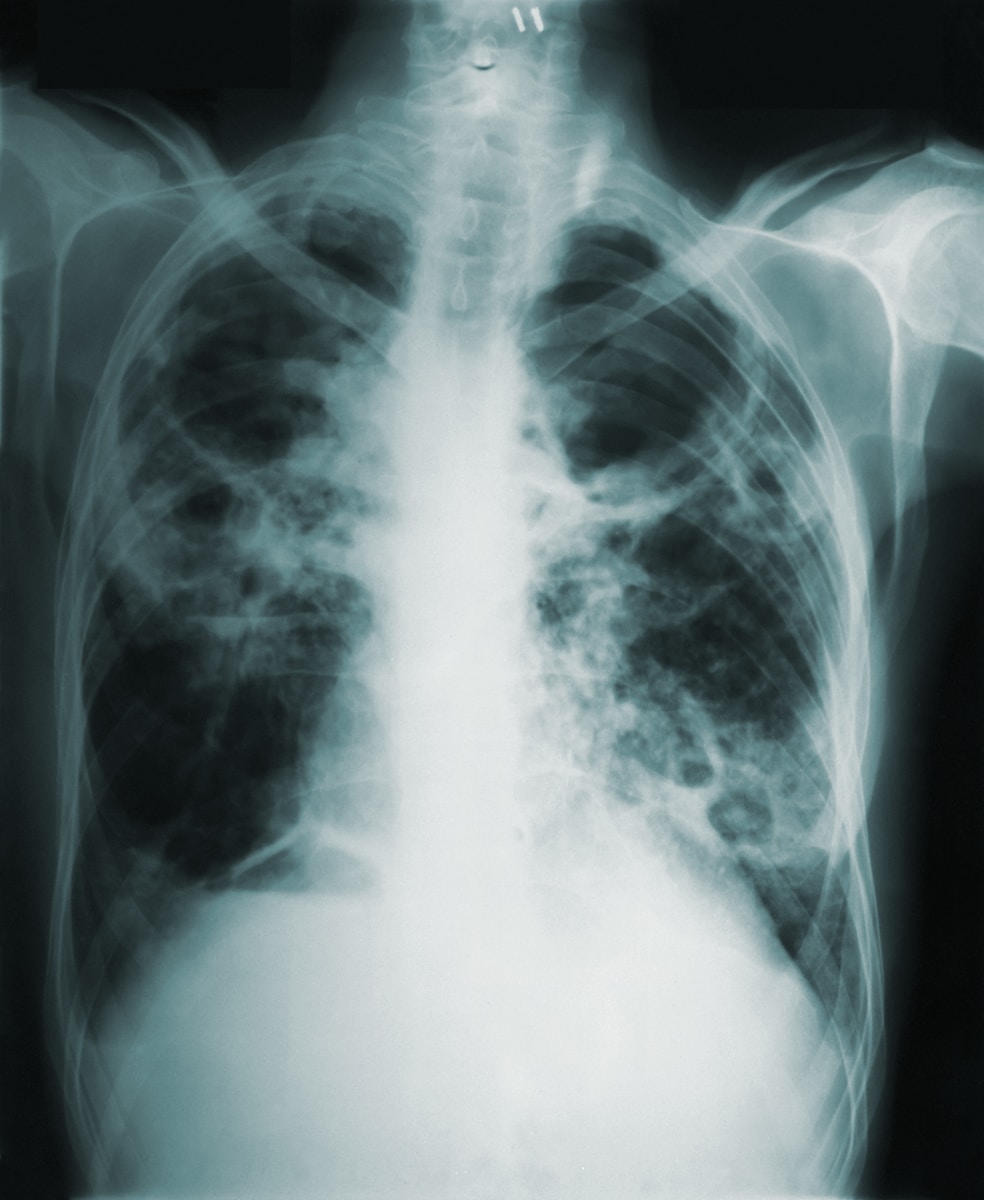

O PÁGINA UM começa, a partir de hoje, a apresentar um conjunto de análises à base de dados da morbilidade e mortalidade do Portal da Transparência do Serviço Nacional de Saúde (SNS). Neste primeiro artigo revela-se que, afinal, houve muitas mortes por covid-19 que “escaparam” a tratamento hospitalar, e que a pressão sobre o SNS foi, na verdade, com excepção de um curto período (Dezembro de 2020-Fevereiro de 2021), atipicamente baixo nos dois anos de pandemia. E essa situação mostra-se evidente sobretudo a partir de Março do ano passado.

São dados oficiais. Indesmentíveis pelo Ministério da Saúde. Os registos da morbilidade e mortalidade hospitalar do Portal da Transparência do Serviço Nacional de Saúde (SNS) revelam que, durante os dois anos da pandemia (2020-2021) morreram afinal menos pessoas nos hospitais portugueses do que nos dois anos anteriores (2018-2019).

Ora, aquilo que se verificou – pegando nos registos das mortes por todas as causas ocorridas em meio hospitalar – é que, com excepção de um curto período, entre Dezembro de 2020 e Fevereiro de 2021, o SNS não denotou uma sobrecarga. No caso de Janeiro de 2021 houve mesmo um evidente colapso com um recorde de 8.590 óbitos. No período anterior à pandemia – e desde 2017, com informação na base de dados do SNS –, nos piores meses contabilizavam-se cerca de seis mil óbitos em meio hospitalar, sobretudo no mês de Janeiro, estando associado aos surtos gripais (causadores de mais mortes por doenças respiratórias) e ao frio (adjuvante de doenças mortais do aparelho circulatório).

Porém, excluído esse trimestre, ninguém que agora surgisse por aqui sem saber que houve uma pandemia poderia dizer que o SNS esteve sob pressão. Pelo contrário: desde Março do ano passado, o número de óbitos mensais registados nos hospitais do SNS foi sempre atipicamente baixo (sempre abaixo dos 4.000). E esta situação observou-se sobretudo com chegada das estações associadas a uma maior mortalidade (Outono e Inverno). Por exemplo, em Dezembro passado apenas se contabilizaram 3.793 óbitos. No mês homólogo dos três anos anteriores à pandemia, os óbitos em meio hospitalar foram muito superiores: 5.089 em 2017, 4.637 em 2018 e 4.561 em 2019.

O mês de Janeiro deste ano – que já consta da base de dados do SNS – surge com 3.461 óbitos, um valor extraordinariamente baixo, tanto mais que chega a ser inferior aos meses de Verão pré-pandemia.